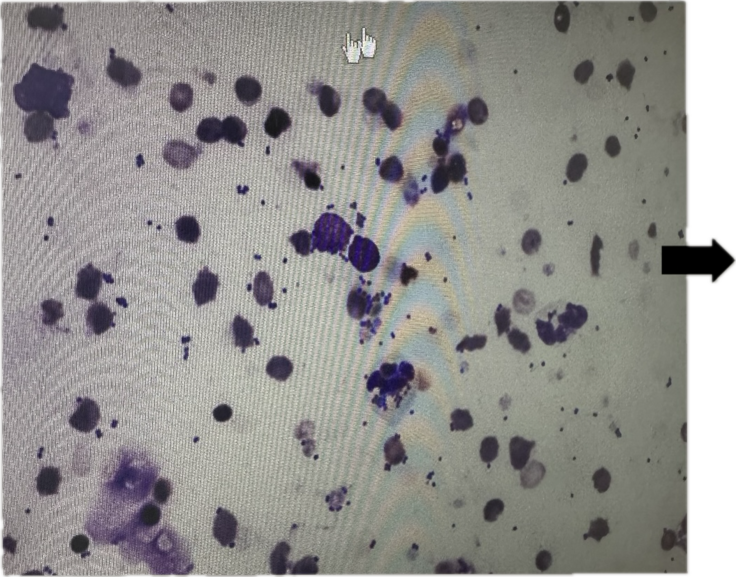

大きい丸が『赤血球』、小さなポツポツが『菌』

結果は——菌の数は大きく減少。ただし、完全に消えたわけではありませんでした。

そこで、さらなる効果を求めて新しい抗生物質を処方していただくことに。